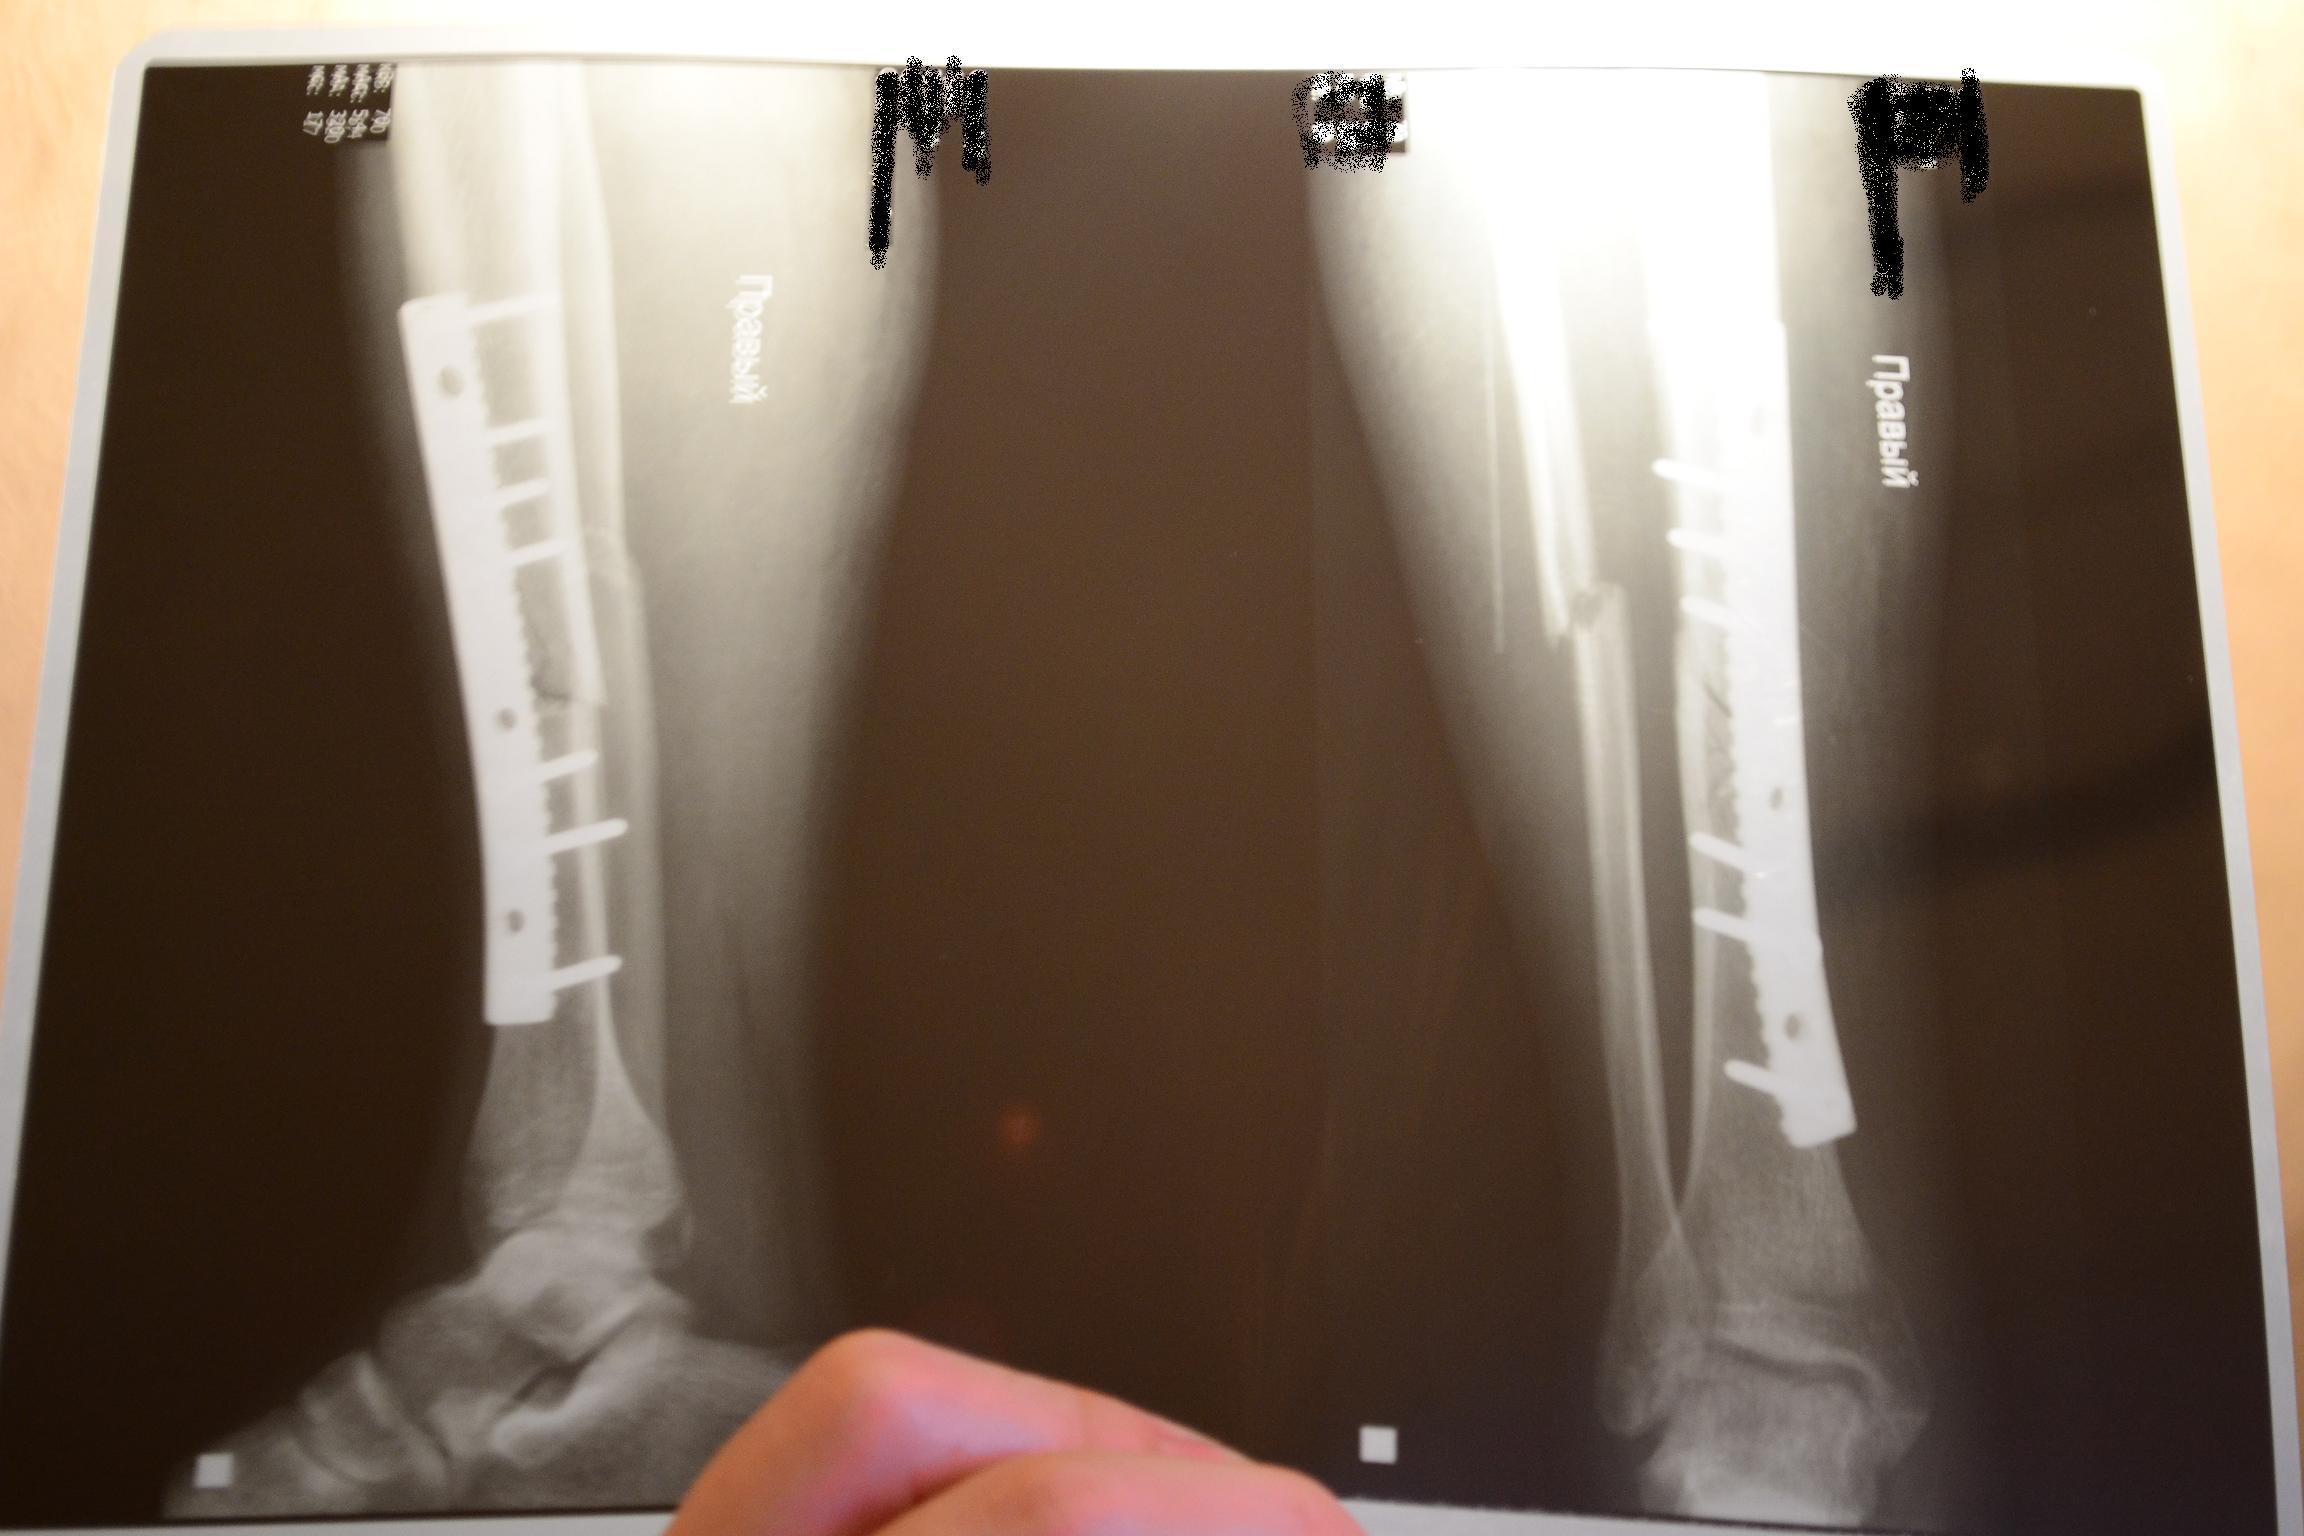

Перелом большой берцовой кости - серьезное повреждение, сопровождающееся болезненными ощущениями и нарушением функции ноги. На этой странице вы найдете много фотографий, позволяющих вам более детально изучить эту травму.

Интрамедуллярный остеосинтез

Чрескостный остеосинтез лодыжки

Остеосинтез двухлодыжечного перелома

Здесь представлены медицинские изображения переломов большой берцовой кости, сделанные врачами в процессе диагностики и лечения. Вы сможете увидеть, как выглядит этот тип травмы на рентгеновских снимках и других медицинских изображениях.